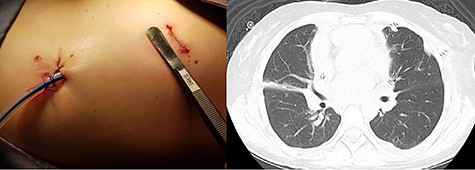

Before surgery, the cystic tumor was punctured in a separate session with ultrasound-guided technique by a pulmonologist to generate space in the thoracic cavity, obtaining a thick yellowish fluid (Fig. 3). After that, surgical treatment was indicated with a VATS approach. The camera was inserted through a 1 cm incision in the seventh intercostal space (ICS) on the posterior axillary line, a small working incision was made in the fourth ICS between anterior and midaxillary lines for thoracoscopic instruments. Upon entering the left thorax, a 15 cm diameter cystic tumor was observed, the tumor was firmly adherent to the pericardium, contralateral pleura and great vessels. A small part of the lung was resected en bloc together with the cystic tumor, which was removed successfully without intraoperative complications. A 24-French silicon closed drain was left in place.

After surgery, the patient developed right lobar atelectasis (Fig. 4), which was treated with respiratory physiotherapy and rehabilitation. She was discharged 8 days after surgery and the drain was removed during the follow-up examination on the 13th postoperative day. Histologic examination showed a mature cystic teratoma without malignant characteristics (Fig. 5). No recurrence was found during a 24-month follow-up.

(A) Immediate postoperative view. (B) Postoperative CT scan showing absence of the tumor and a right lobar atelectasis.